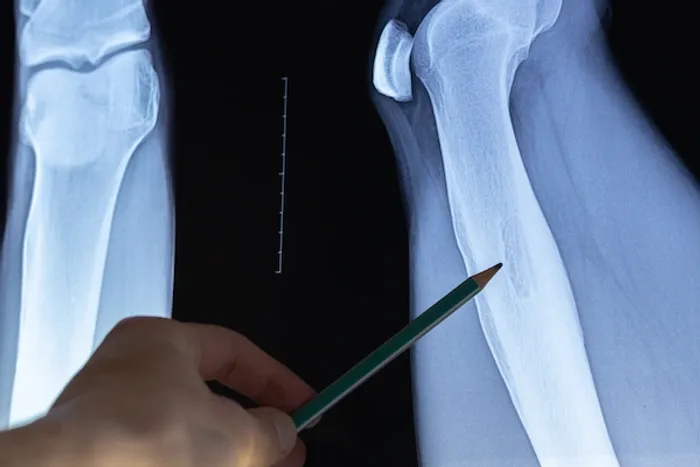

X-ray: This imaging test provides detailed images of your bones. An osteoid osteoma usually appears as a thickened area of bone with a small central core.

Osteoid osteomas are most commonly found in the long bones, such as the tibia (shin bone) and femur (thigh bone). They can also occur in other parts of the body, including the arms, hands or fingers, feet or ankles, and spine.